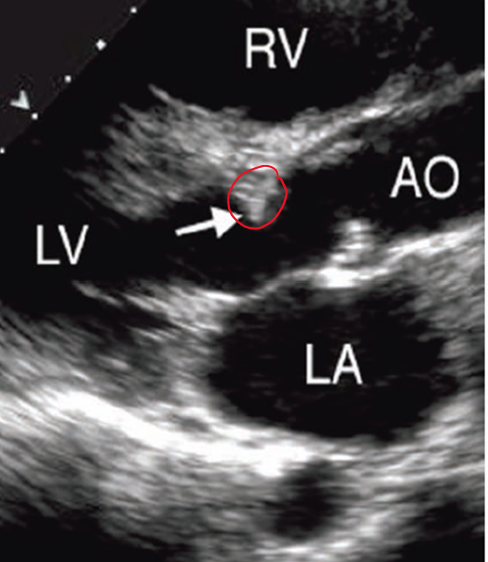

what is raphes?

lines present where the valve does not open (typically in larger leaflet) so when closed valve looks trileaflet

should bicuspid ao valve be diagnosed in diastole or systole?

systole because in diastole when it is closed the raphe may make it appear trileaflet

what does a bicuspid valve look like in PSAX?

in systole only 2 leaflets “open”